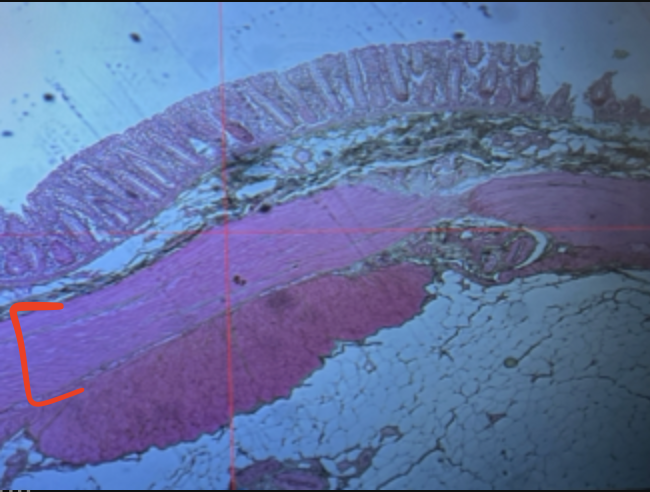

esophagus

lumen

mucosa

mucosal epithelium

lamina propria

muscularis mucosa

submucosa

muscularis (externa)

serosa/adventitia